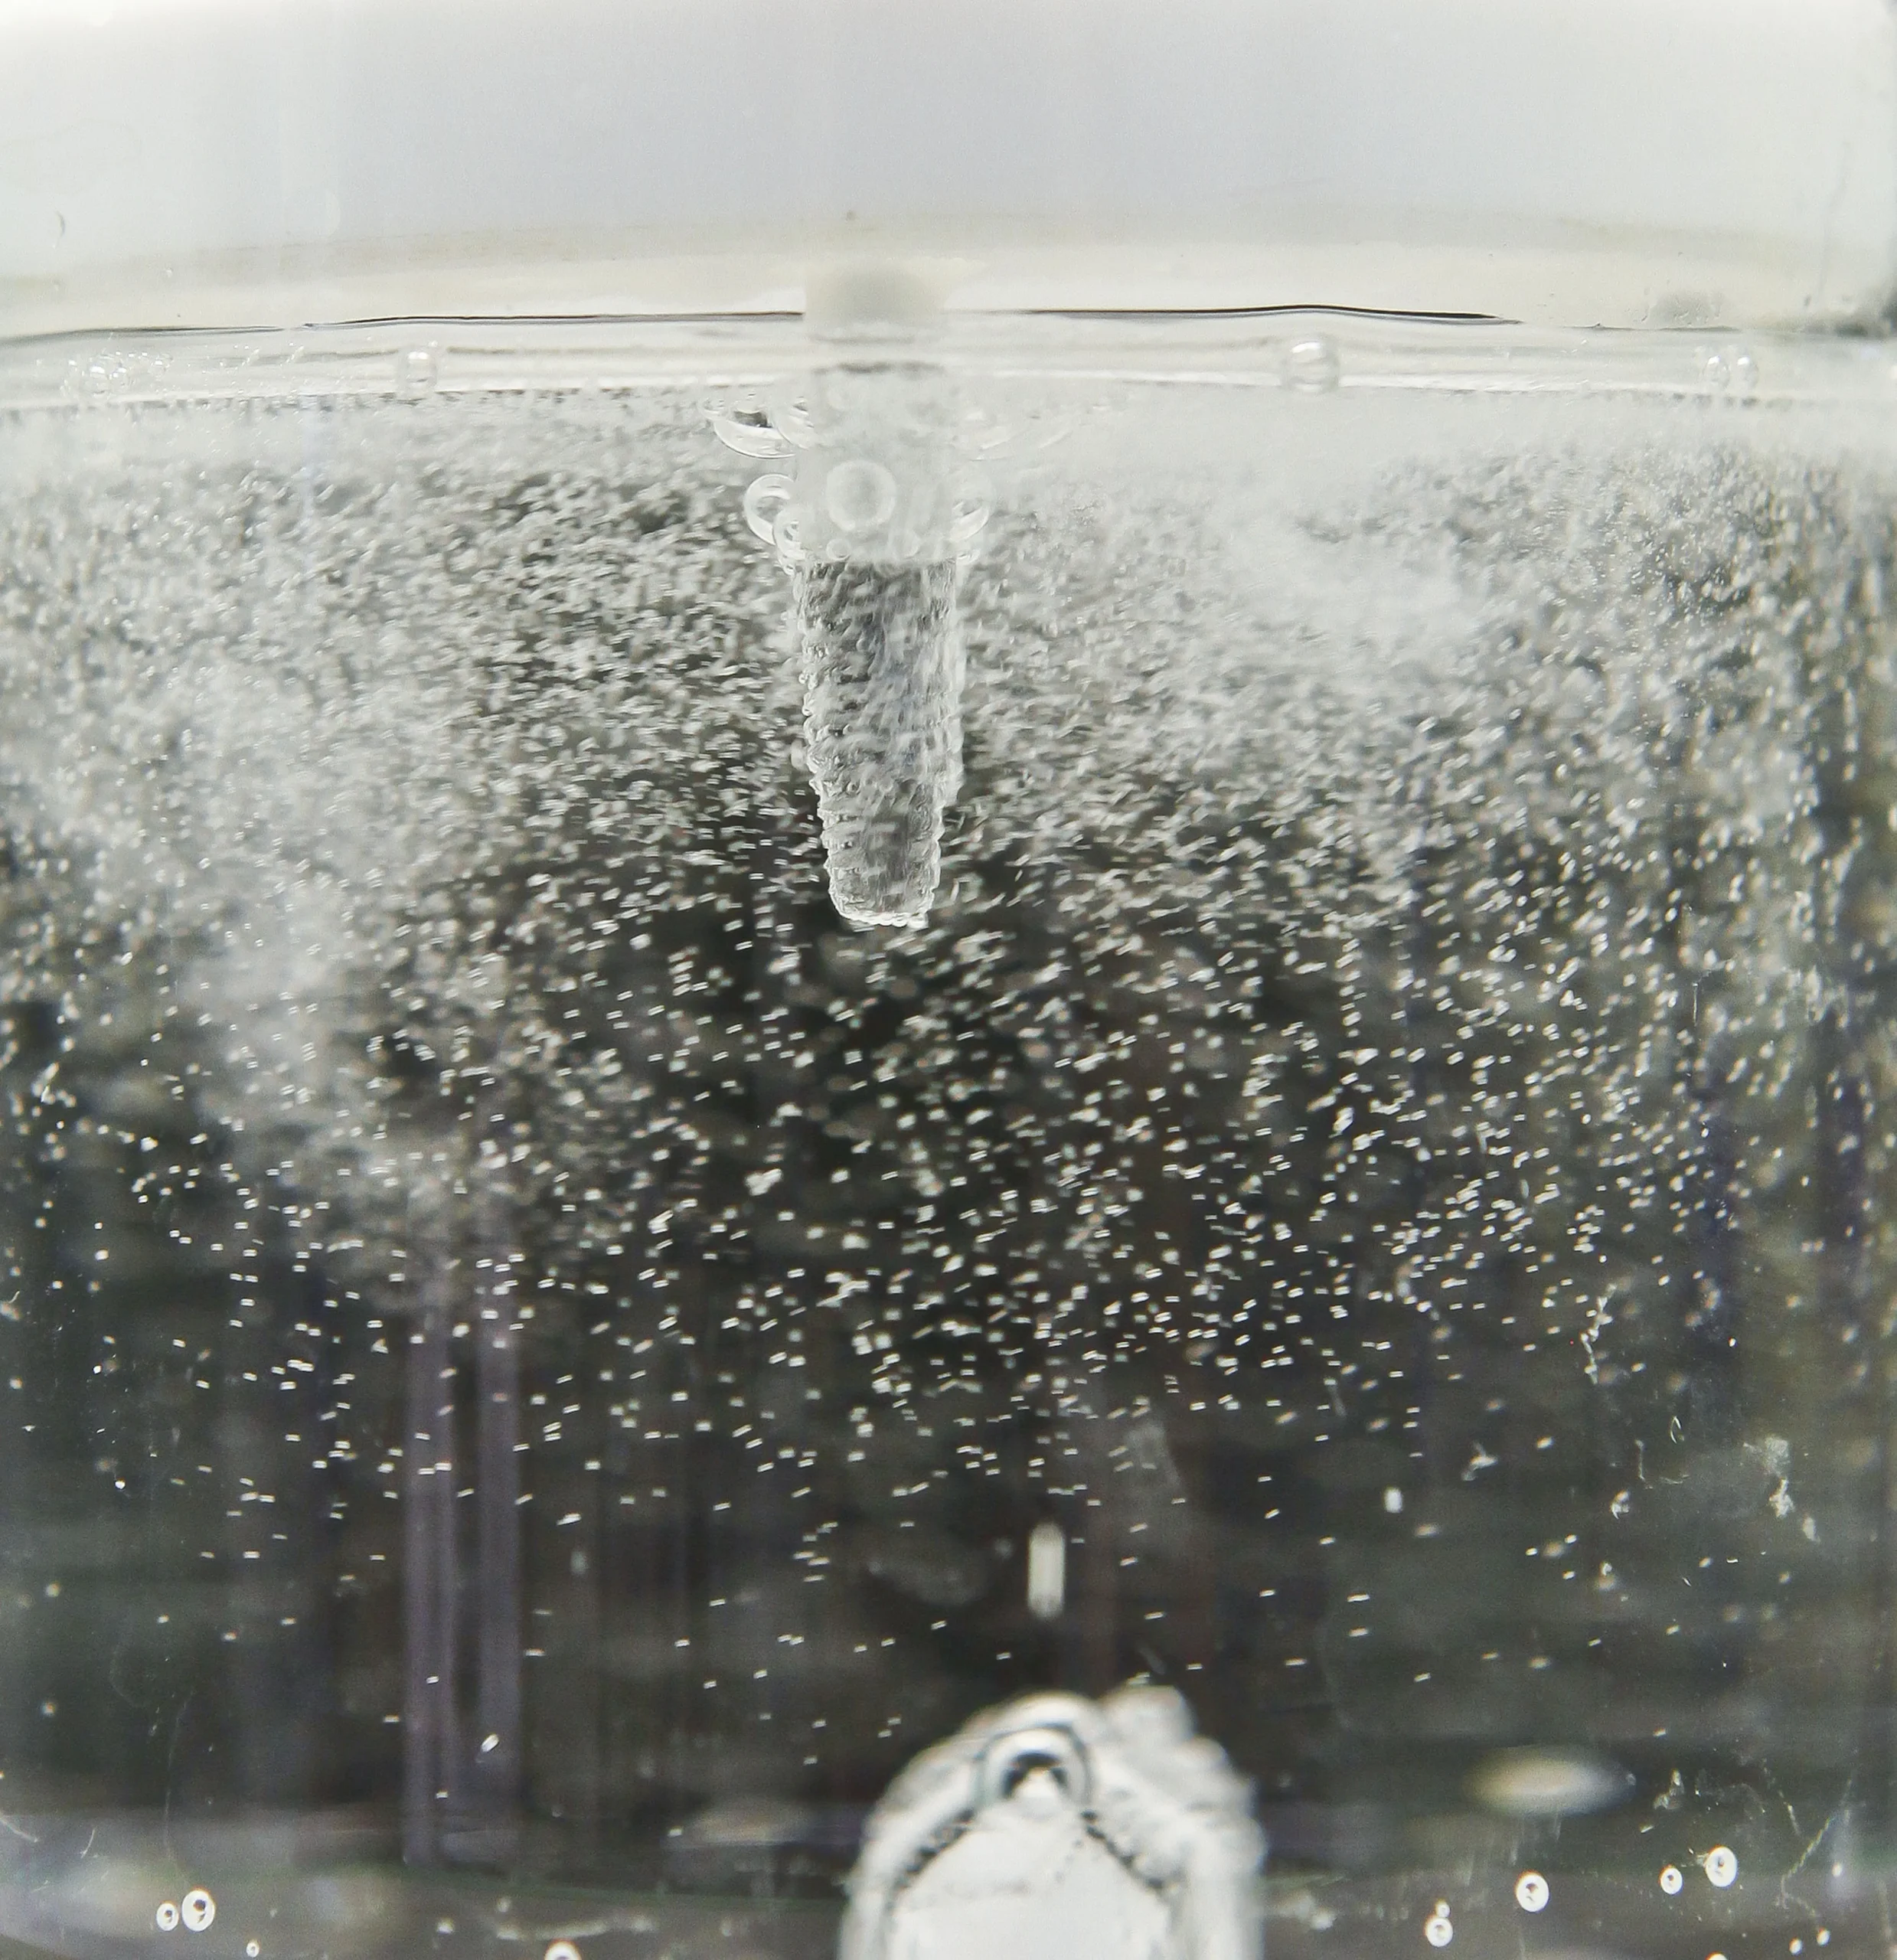

Công nghệ sb/la độc quyền

Công nghệ SB/LA độc quyền (thổi cát hạt lớn và ăn mòn axit) được Ritter thiết kế để đẩy nhanh quá trình tích hợp xương của Implant và tối ưu hóa quá trình lành thương bằng cách mang lại cả lợi thế về mặt cơ sinh học và sinh học. Quá trình này, sử dụng các hạt thô hơn trên công nghệ xử lý bề mặt SLA, tạo ra các vết mài mòn vi mô từ 1-5 µm và các vết mài mòn vĩ mô từ 20-40 µm trên bề mặt. Những vết mài mòn này tạo ra một cấu trúc đa tầng giúp tăng cường sự bám dính của nguyên bào xương (tế bào xương).

Ngay sau khi đặt Implant bề mặt tạo ra các khoảng trống lớn cho phép Protein huyết tương và máu được hấp thụ mạnh mẽ vào các vi lỗ của Implant. Nó cũng tăng cường hoạt động của tế bào xương bằng cách cung cấp độ nhám bề mặt đồng đều hơn.

Độ nhám vi mô và vĩ mô rộng hơn

Bề mặt SB/LA cung cấp độ nhám rộng hơn ở cả cấp độ vi mô và vĩ mô. Độ nhám bề mặt từ 1-5 µm ở cấp độ vi mô và 20-40 µm ở cấp độ vĩ mô cho phép các tế bào xương liên kết chặt chẽ và nhanh hơn với bề mặt.

Tăng tỷ lệ tiếp xúc xương

Bề mặt SB/LA hỗ trợ sự ổn định lâu dài bằng cách tăng tỷ lệ tiếp xúc giữa implant và xương (tiếp xúc xương với implant, BIC).

Khả năng tương thích sinh học

Bề mặt SB/LA được phát triển để tối ưu hóa khả năng tương thích sinh học. Nó cung cấp bề mặt thuận lợi hơn cho các tế bào xương và giảm nguy cơ biến chứng như viêm quanh implant.

Tỷ lệ tích hợp xương sớm

Bề mặt SB/LA thúc đẩy quá trình lành thương sớm của mô xương xung quanh implant. Các nghiên cứu đã chỉ ra rằng hoạt tính sinh học của bề mặt SB/LA cao hơn bề mặt SLA.

Độ đồng nhất bề mặt

Bề mặt SB/LA có cấu trúc nhám đồng đều hơn nhờ lớp oxit titan ưa nước được tạo ra. Điều này làm tăng cả độ ổn định cơ học và khả năng tương thích sinh học.

Tỷ lệ thành công dài hạn

Implant với bề mặt SB/LA mang lại tỷ lệ thành công lâm sàng lâu dài cao hơn. Đây là một lợi thế đáng kể, đặc biệt là trong các trường hợp khó hoặc bệnh nhân có mật độ xương thấp.